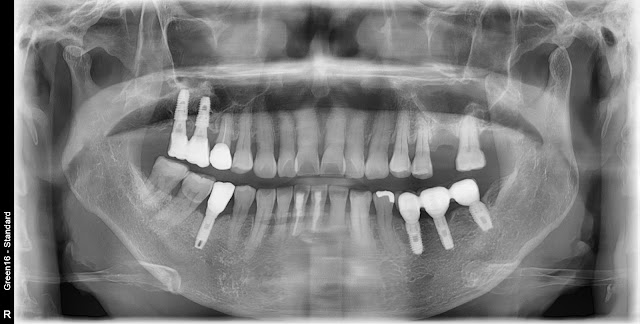

This year's patient is a 67-year-old woman.

The maxillary left first molar was extracted due to periodontal disease.

A photo taken approximately 3 months after the extraction.

Despite the limited remaining bone, I have decided to proceed with a crestal approach for implant placement.